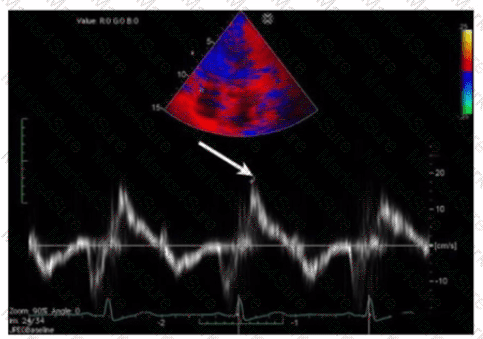

Which next step is appropriate after obtaining the Doppler signal in this image?